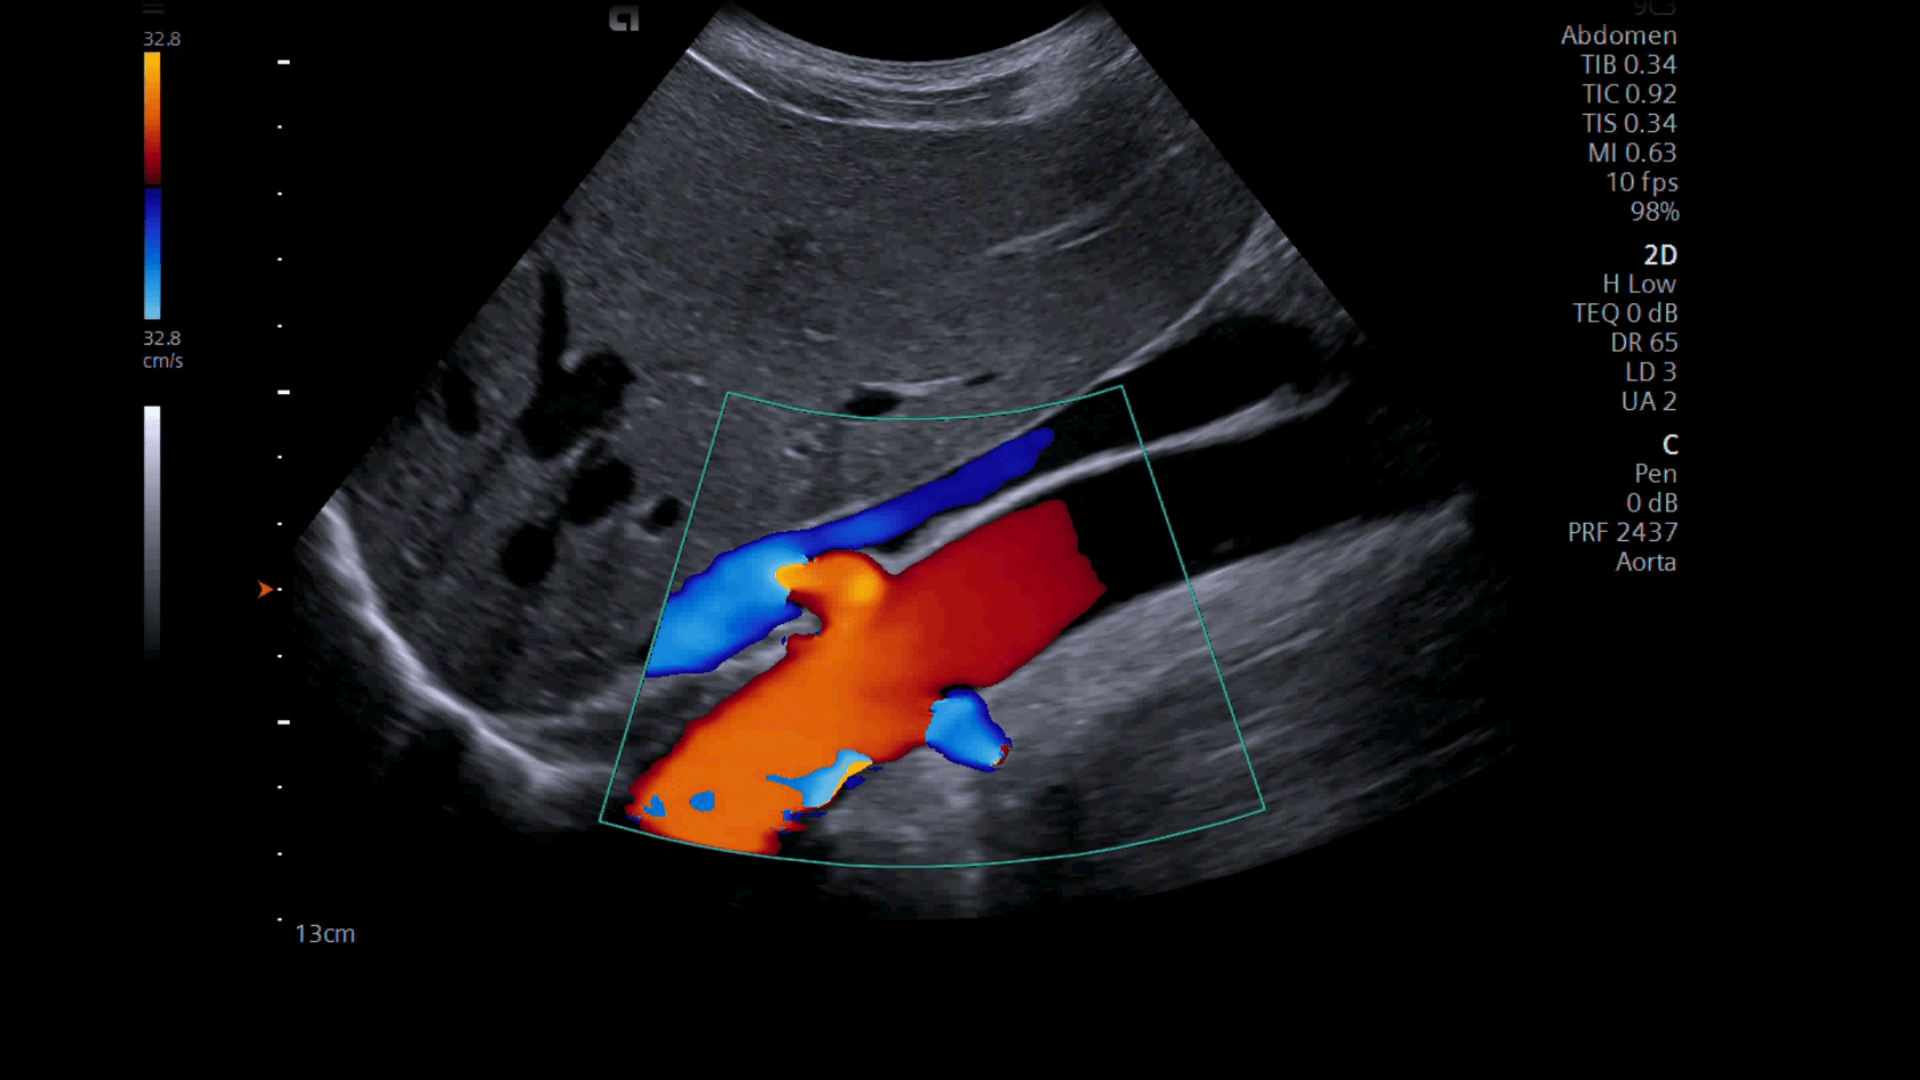

wallpaperaccess.comultrasound epiq elastografia utilizata cand vascular expands portfolio

wallpaperaccess.comultrasound epiq elastografia utilizata cand vascular expands portfolio

Colourful Image Of Modern Ultrasound Monitor Stock Photo - Image Of

www.dreamstime.comultrasound

www.dreamstime.comultrasound

Colourful Image Modern Ultrasound Monitor Ultrasonography Stock Photo

www.shutterstock.comUltrasound Wallpapers - Top Free Ultrasound Backgrounds - WallpaperAccess

www.shutterstock.comUltrasound Wallpapers - Top Free Ultrasound Backgrounds - WallpaperAccess